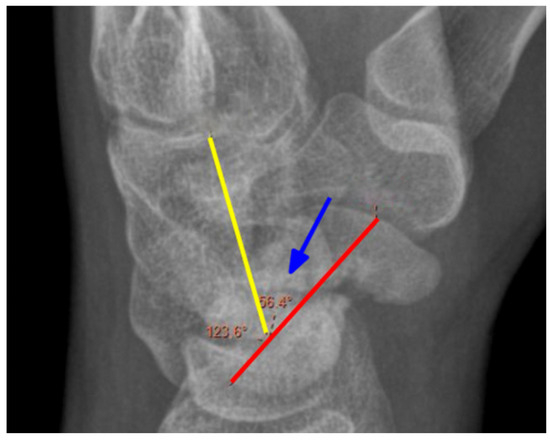

2.2. Radiological Assessment

| CLA | Capitolunate angle |

| SLA | Scapholunate angle |

| SCA | Scaphocapitate angle |